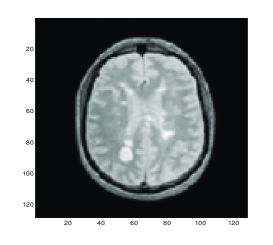

For comparison, the transformed template images for the diffeormorphic demon method, linear, mean and Gaussian curvatures are shown in Figures 2 (a), (b), (c) and (d) respectively. We can observe that there are some differences of these images inside the red boxes where only Gaussian curvature delivering the best result of the features inside the boxes.

Refer to caption

(a) Model D

(b) Model LC

(c) Model MC

(d) Gaussian curvature

Figure 2: Test 1 (X-ray hand). Comparison of Gaussian curvature with competing methods. The transformed template image using (a) Model D, (b) Model LC, (c) Model MC and (d) Gaussian curvature. Note the difference of these three images inside the red boxes.